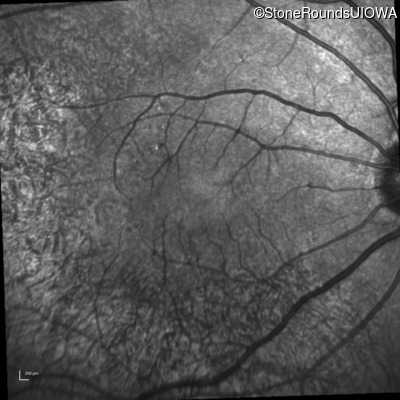

Infrared Fundus Photograph - Right - 20/20 -1

Exemplar